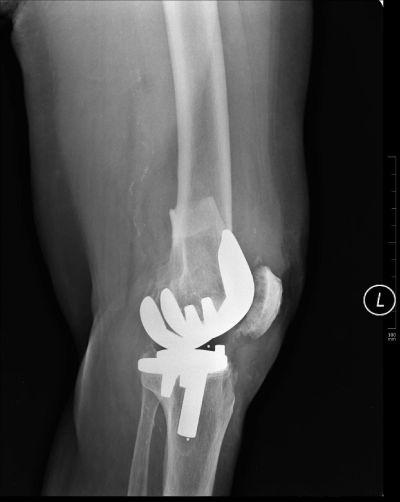

With the patient under Laryngeal Mask Airway (LMA) anesthesia, a CACEF System (The Smart Correction ®) was applied (Figure 3). The fixator was performed with the patient in the supine position under image-intensification guidance. Two half-pins and a tensioned wire were inserted through the distal ring and distal to the fracture line. Two half-pins were inserted into the proximal ring and proximal to the fracture line. The device consisted of 6-strut construct for connection of special frames. We didn’t make any effort for reduction intra operatively. So operative time was just 35minutes. The patient tolerated surgery well and made rapid recovery postoperatively.

Figure 3: Radiograph showing the management of the fracture by computer assisted circular external fixation.